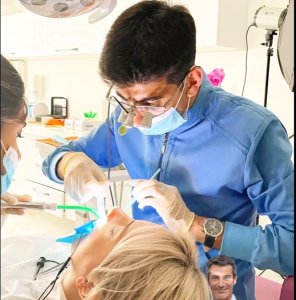

Коли я прибув до клініки, мене зустрів перекладач, який все пояснив. Я зустрівся з лікарем, який був справжнім експертом у своїй галузі. Клініка була бездоганно чистою, сучасною, і персонал також був таким же.

У клініці я ще раз обговорив свій план лікування, оскільки виявилося, що мені знадобиться додаткове лікування кореневих каналів і пломбування. Я також підвищив якість коронок. Я заплатив половину вартості лікування наперед, а решту залишив на кінець. Лікування зайняло 6 днів, і я був у клініці 5 з них. Загальний час перебування в клініці кожного дня коливався від 1 години до 5 годин. Мені виписували антибіотики та знеболюючі препарати.

Не сподівайтеся, що це буде безболісний процес. Це стоматологічна робота. Однак клініка і персонал суперпрофесійні, і вам нададуть знеболення.